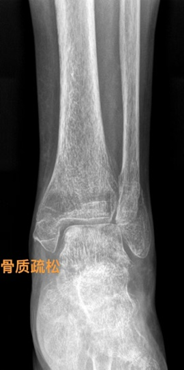

(7)骨质疏松:指单位体积内骨组织的含量减少,即骨组织内的有机成分和无机成分都减少,但两者的比例仍属正常。常见于中老年妇女。